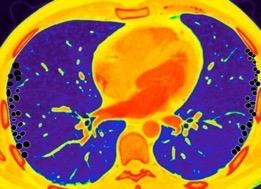

Tromboembolismo pulmonar.

Frecuencia del derrame:

Rx: 32%. TC: 47%

Unilateral. 85%

< 1/3 del hemitórax: 90%

Todos exudados

58% con eritrocitos

21% tabicación lo que causa demora en el diagnóstico

TEP. Empiema pleural. Atelectasia redonda

Porcel JM et al. Analysis of pleural effusions in acute pulmonary embolism: radiological and pleural fluid data from 230 patients. Respirology 2007/ Iguchi T et al. Desquamation of the subpleural lung parenchyma caused by empyema after pulmonary embolism: A case report. Respirol Case Rep. 2022 .